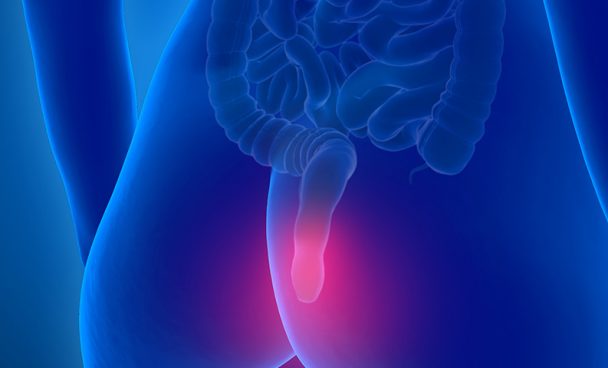

Anal Kanal Kanseri hakkında bilgi

Anal Kanal Kanseri, anüs ve anal kanalın iç yüzeyinde gelişen kanser türüdür. Bu kanser, genellikle rektumun son kısmında veya anüsün çevresindeki dokularda oluşur. Anal kanal kanseri nadir görülse de, bazı risk faktörleri ve belirtilerle tanımlanabilir.

Belirtiler

Anal kanal kanserinin belirtileri şunlar olabilir:

- Anal bölgede kütle veya yumru: Dışkılama sırasında hissedilen anormal yapılar.

- Kanama: Dışkılama sırasında veya anüs bölgesinde kanama.

- Ağrı: Anal bölgede sürekli veya aralıklı ağrı.